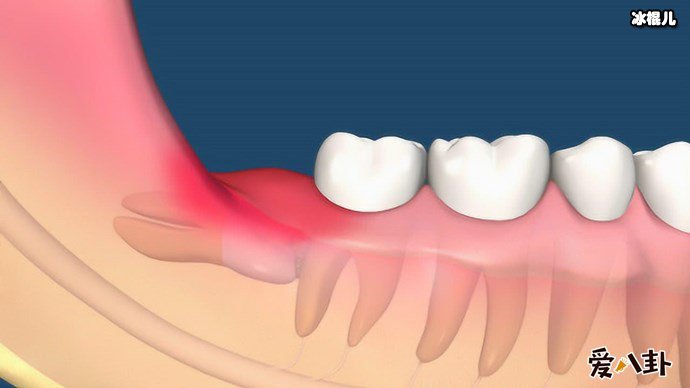

现代人对于长智齿这件事是束手无策的,不少人都被长智齿所折磨,那么长智齿疼又应该怎么办呢,长智齿疼的时候有什么小窍门吗?说到长智齿肯定就是现代人最为头疼的事了,这个连医学都解决不了的问题几乎每个人都被折磨的不行,不少网友说长智齿这个事堪比绝症痛不欲生,但是大部分的人长智齿这个事实避免不了的,所以智齿这个折磨人类的小妖精又是什么呢,它是普通牙齿吗

初期的智齿

说到智齿也就是人们说的智慧齿,智齿实际上是口腔中的第三大臼齿(一般人都有第一和第二大臼齿),因为张智齿的年龄大都是在刚成年的时候,有了智慧所以俗称智慧齿,一般来说有四只智慧齿分别形成始于上下颚骨中,智齿跟其他牙齿一样,但是智齿很不一样的是智齿是最后长出的臼齿,一般智慧齿成形成于9岁而齿冠则于大约14岁形成,并在青春期末长出于口腔中。

不少人都被智齿折磨的痛不欲生,所以么长智齿疼又应该怎么办呢,有这么一个小窍门,如果疼的时候可以含点冰块缓解疼痛,或者用冰块在脸部外敷,一般平时在饮食上要注意,吃的太辛辣就会加重疼痛感,而且每天都要注意清洗口腔,避免口腔滋生细菌,导致长智齿的部位发生感染,一般来说长智齿了就应该马上去医院处理拔掉它,不然智齿压迫了神经,不处理就会遭受长期的疼痛折磨还有进一步加重